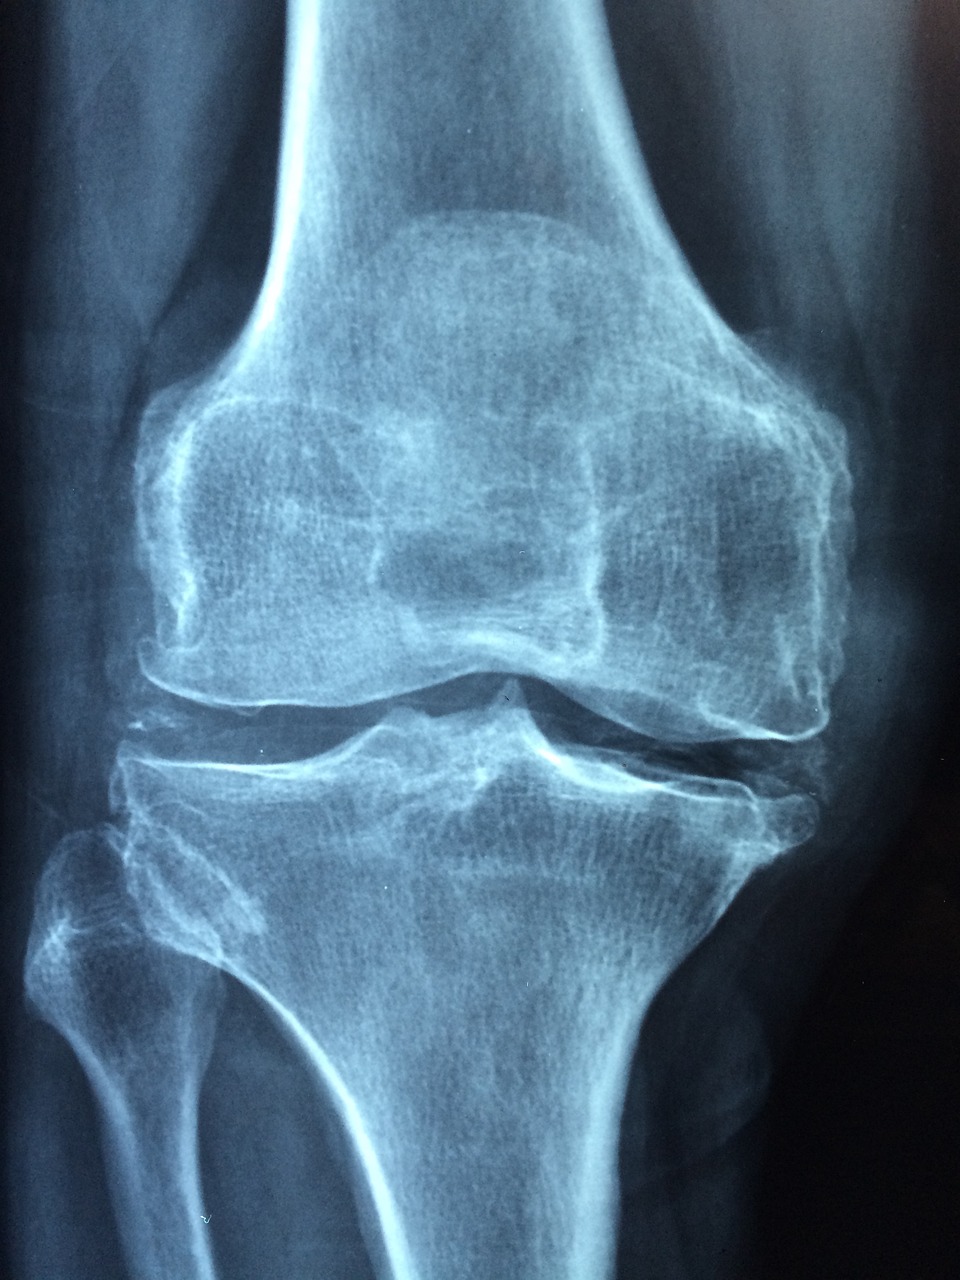

관절염으로 인해 관절의 마모가 발생할 수 있습니다. 이는 관절의 동작에 부담을 주고 보호 기능을 감소시킬 수 있습니다. 또한, 관절염으로 인해 자세에 불편을 느낄 수 있으며, 특히 장시간의 앉아 있는 자세나 힘을 주는 동작에서 불편을 경험할 수 있습니다.

관절의 변형: 마지막으로 조심해야 할 관절염의 징후

진행된 관절염은 관절의 형태와 구조에 변화를 가져올 수 있습니다. 이는 관절의 형태의 변형이나 골절을 초래할 수 있으며, 심각한 경우 관절 운동에 심각한 제한을 초래할 수 있습니다.